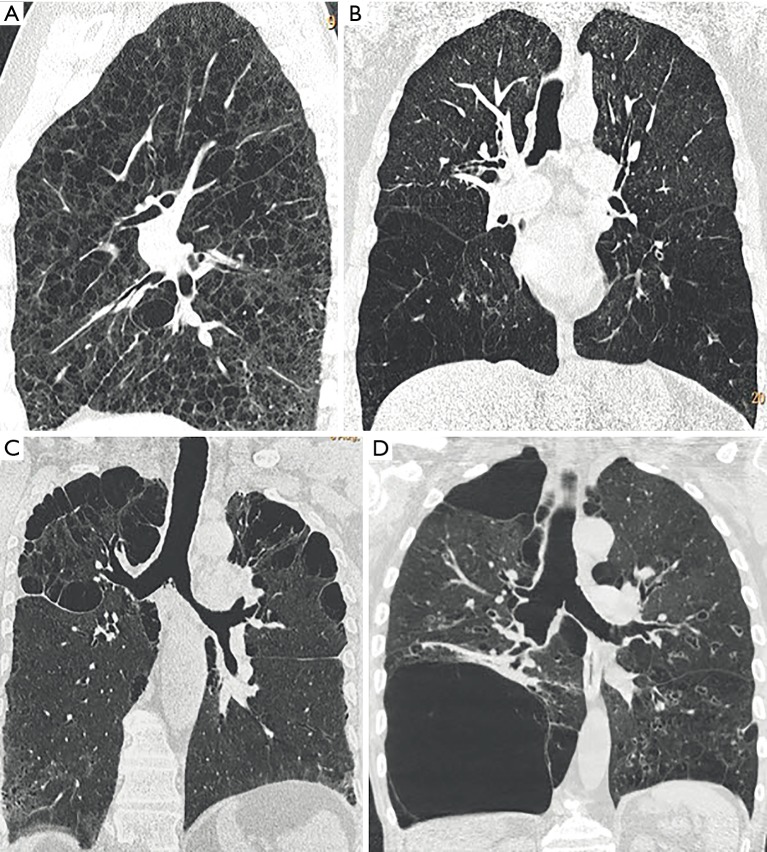

Emphysema is a destruction of the lung parenchyma distal to the terminal bronchiole, which radiographically are seen as destruction and absence of normal lung parenchyma. Three types of emphysema can be distinguished: (I) panlobular, (II) centrilobular, and (III) septal emphysema and can additionally evaluate the severity and distribution of lung changes (26) (Figure 2). Quantification can be performed by visual scoring, semiquantitative using densitometry or by quantification:

Figure 2.

Different emphysema distributions on non-enhanced chest CT. (A) Axial reconstruction in a 63-year-old male patient shows centrilobular emphysema; (B) it shows emphysema in a 58-year-old female patient with panlobular distribution; (C) it shows axial reconstruction in a 67-year-old female patient with paraseptal emphysema; (D) it shows coronal reconstruction in an 82-year-old male patient with bullous emphysema. CT, computed tomography.

But other authors report still a high interobserver disagreement of this technique: in the NETT, all observers had to undergo training on a set of CT. Despite the use of experienced and previously trained chest radiologists, there was still significant inter- and intra-observer variability in emphysema quantification (12). To reduce interobserver variability the presentation of the emphysema can be enhanced by simple methods without the use of dedicated software, as for example with sagittal volume rendering based thin slabs, colour coding the severity and distribution of emphysema. This so called “CT densitometry” (Figure 3) has a higher accuracy compared to multiplanar reconstructions (MPRs) (unpublished data).

Figure 3.

Preoperative imaging before LVR. It shows CT densitometry in a 72-year-old male patient with COPD GOLD III in (A) axial, (B) coronal, and (C) sagittal reconstruction as well as the (D) 3D dataset. The apical predominant distribution of emphysema is highlighted in blue. The higher the score, the higher the presence of emphysema. Lobe area (LAA) and percentage of lobe area to total lung (LAA%). LVR, lung volume reduction; CT, computed tomography; LAA, low attenuation area; COPD, chronic obstructive pulmonary disease; GOLD, Global Initiative for Chronic Obstructive Lung Disease.